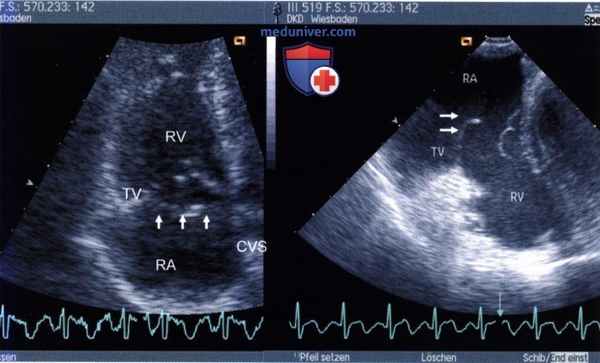

1. Трансторакальная эхокардиография. Трехстворчатый клапан состоит из передней, септальной и небольшой задней створок. Двумерная трансторакальная ЭхоКГ позволяет одновременно визуализировать переднюю и септальную створки в течение всего сердечного цикла. Исследование лучше выполнять из левой парастернальной позиции по короткой оси сердца, а также из апикальной позиции. При допплеровском исследовании трехстворчатого клапана датчик располагают в апикальной, а часто и в левой парастернальной позиции.

С помощью трансторакальной ЭхоКГ при удовлетворительных условиях исследования маленькую заднюю створку трехстворчатого клапана удается рассмотреть лишь при сканировании из парастернальной позиции датчика, который ориентируют на левое плечо вдоль оси «приносящего тракта правого желудочка».

Слева: трехстворчатый клапан при трансторакальной ЭхоКГ у больного 37 лет с прогрессирующей одышкой при физической нагрузке. В правое предсердие выдается дополнительная структура (стрелки), расположенная на отдалении от нормально расположенной створки трехстворчатого клапана. Справа: при ЧПЭ у того же больного выявлен выраженный пролапс передней створки трехстворчатого клапана. CVS - расширенный коронарный синус.